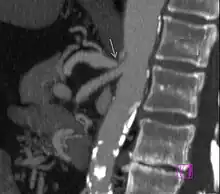

Side views (sagittal plane) of the descending aorta and two of its branches, the celiac trunk and superior mesenteric artery, demonstrate normal and MALS anatomy. Left The median arcuate ligament is normally several millimeters to centimeters superior to the origin of the celiac artery. Right In MALS, the ligament is anterior, rather than superior, to the celiac artery, resulting in compression of the vessel and a characteristic hook-shaped contour.

Further evaluation and confirmation can be obtained via angiography to investigate the anatomy of the celiac artery.[5] Historically, conventional angiography was used, although this has been largely replaced by less invasive techniques such as computed tomography (CT) and magnetic resonance (MR) angiography.[2][5] Because it provides better visualization of intra-abdominal structures, CT angiography is preferred to MR angiography in this setting.[5] The findings of focal narrowing of the proximal celiac artery with poststenotic dilatation, indentation on the superior aspect of the celiac artery, and a hook-shaped contour of the celiac artery support a diagnosis of MALS.[2] These imaging features are exaggerated on expiration, even in normal asymptomatic individuals without the syndrome.[2]

Proximal celiac artery stenosis with poststenotic dilatation can be seen in other conditions affecting the celiac artery.[2] The hook-shaped contour of the celiac artery is characteristic of the anatomy in MALS and helps distinguish it from other causes of celiac artery stenosis such as atherosclerosis.[2] This hooked contour is not entirely specific for MALS however, given that 10–24% of normal asymptomatic individuals have this anatomy.[2]